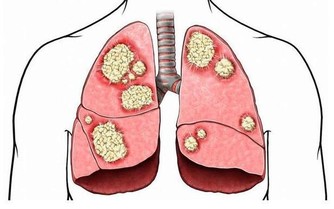

以上提到的習慣,都可能引起腎單位損傷、腎功能不斷惡化。

其最終結果,就是導致腎臟基本功能喪失,機體內代謝廢物的排泄以及水、電解質和酸鹼平衡等調節出現嚴重障礙,這就是醫學上所說的尿毒症。

當然,慢性腎功能衰竭是由長期病變逐步發展而成的,所以起病常常比較隱匿。

再加上腎的儲備量相當大,平時只需1/4的腎單位工作就能滿足機體需要,只有在腎臟損傷達3/4以上,患者才會出現症狀。

如果患者剛好耐受性較好,又沒做定期體檢,腎功能的減退大多難以早期發現。